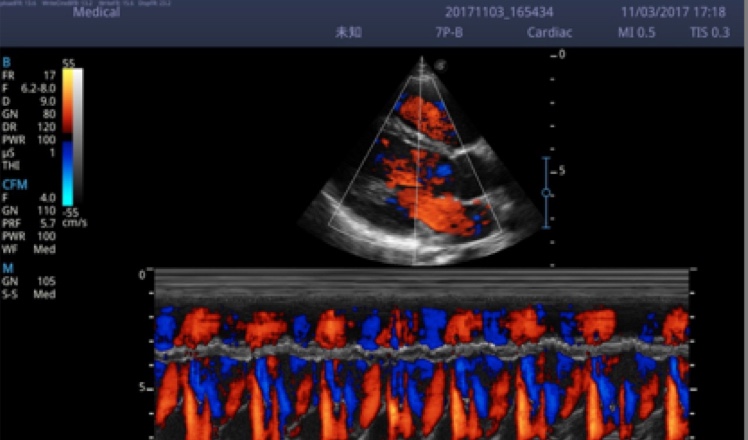

X5采用前端的超声专用芯片,将台式机大规模集成电路完美压缩在笔记本超声的精巧下,提高了系统的运算速度,加载μ-Scan微米成像、脉冲反相谐波等技术,带来优异的临床表现,清晰呈现高分辨率二维图像和层次丰富的血流图像

X5具备实时宽景成像、穿刺增强、彩色M型、组织多普勒等多种高级成像功能,全方位满足多个科室的诊断需求,整机系统向智能化跨越